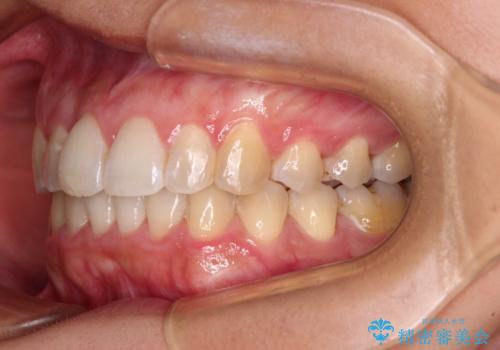

前歯のデコボコをインビザラインでスッキリと仕上げる

- 上下前歯のデコボコと奥歯の銀歯を気にして来院された患者様です。

口元をインビザラインにより歯列を整え、その後に失活している奥歯をオールセラミッククラウンにて補綴治療することとしました。

長時間のマウスピース装着に協力いただき、自然な口元に仕上げることができました。

気になっていた銀歯もオールセラミッククラウンで本物の歯のようになり、患者様には大変満足していただきました。